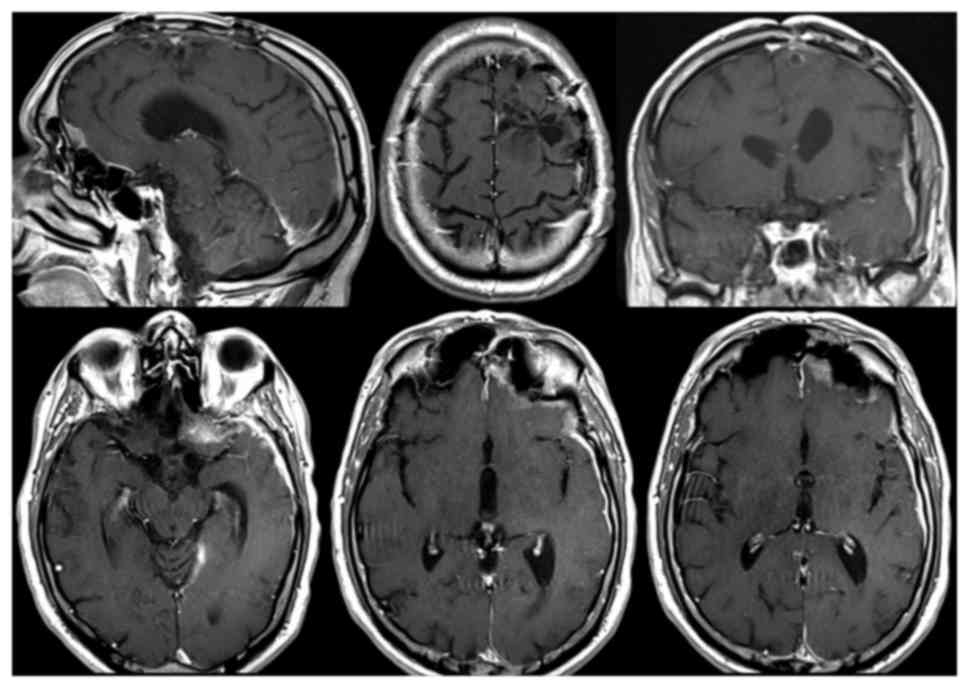

In December, on the 10th post-operative month, a brain MRI performed shows a massive disease progression with increased of leptomeningeal thickening of the left cerebral hemisphere, which presents a multinodular contrast-enhancing aspect (Fig. 6). The nodulations have a size between 0.7 and 2.9 cm and the major nodules are those of the temporal-insular (2.9 cm) and parietal lobe (2.6 and 1.8 cm) with loco-regional parenchymal spread. In the left-frontal area, at the level of the previous craniotomy, a contrast-enhancing leptomeningeal thickening was detected, attributable to local recurrence of the disease. At the end of the 10th postoperative month the patient died for the evolution of the disease. Informed consent was obtained from the parents of the subject for participation in the present study.

Figure 6.

Contrast-enhanced brain MRI at postoperative month 10. Following 3 cycles of carboplatin and etoposide chemotherapy, brain MRI revealed that the left frontal paracentimetric centronecrotic nodule was no longer evident. Recurrence of the frontotemporal and frontobasal ‘en plaque’ localization as well as the evidence of two novel left parietal localizations were presented with a dural implant. MRI, magnetic resonance imaging.